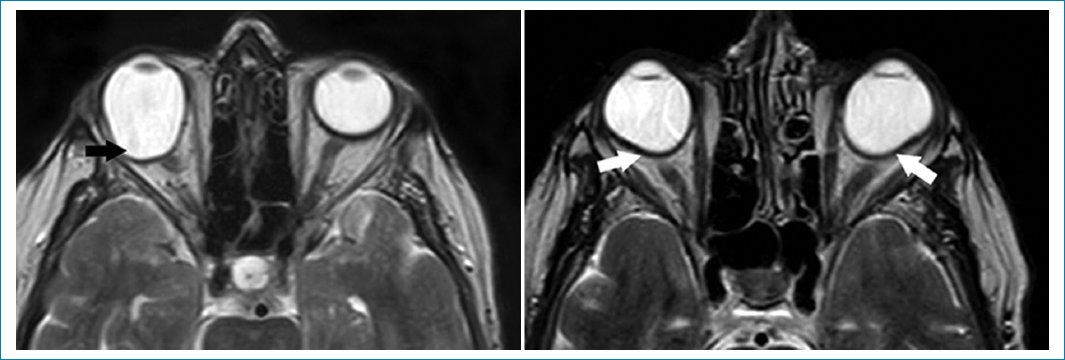

El adelgazamiento asociado a distensión de las membranas esclero-uveales, que como consecuencia genera un aumento de los diámetros anteroposteriores del globo ocular, se conoce como estafiloma24. El estafiloma puede ser unibilateral o bilateral y estar asociado a miopía del plano axial24,25. Se produce, entre otras causas, posterior a un traumatismo, radioterapia, cirugía, miopía o glaucoma24,25. Es bien apreciado en el plano axial en secuencias ponderadas en T2 (Fig. 6).

Figura 6. Imágenes potenciadas en T2. Cortes axiales en los que se evidencia elongación del diámetro antero-posterior de los globos oculares. Compatible con estafiloma (flechas).

La ptisis bulbi es la atrofia, asociada a calcificaciones, del globo ocular, secundaria a traumatismo o procesos infecciosos/inflamatorios previos26.

El globo ocular se aprecia heterogéneo, tanto en secuencias ponderadas en T1 como T2, con calcificaciones groseras asociadas. No es necesaria la administración de gadolinio (Fig. 7)27.

Figura 7. Imágenes potenciadas en T2. Cortes axiales. Se aprecia alteración y deformación del globo ocular, compatible con ptisis bulbi (flechas).